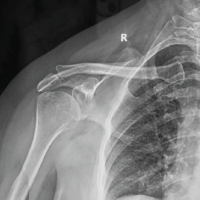

A 65-year-old male farmer presented to the outpatient department with complaints of swelling and persistent pain in the right foot, particularly over the third toe. The patient had been experiencing localized swelling and pain for the past 4–6 weeks, which did not subside despite treatment with antibiotics and analgesics prescribed by his local practitioner. The patient, a farmer by profession, lives with his spouse in a rural setting. His occupation, which involves significant physical activity, including walking, standing, and heavy lifting, likely contributed to the stress on his feet. He has no significant history of smoking or alcohol use. The patient reported a prior history of minor trauma to the right foot 5 years ago, which was managed conservatively with no long-term complications. Two years ago, the patient experienced similar swelling in the same foot, for which an incision and drainage procedure was performed at an outside hospital. Still, there were no subsequent issues after the procedure. At the time of presentation, the patient denied any systemic symptoms such as fever, weight loss, or malaise. He also reported no history of chronic conditions like diabetes, hypertension, or autoimmune disorders. The patient was not taking any long-term medications except for those prescribed for pain and swelling during the current episode. He had no prior history of significant illnesses or surgeries other than the previous minor trauma and surgical intervention on his right foot (Fig. 1-7).